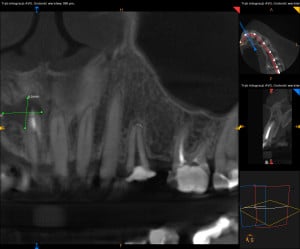

Dokumentacja RTG

- CBCT przed i po zabiegu